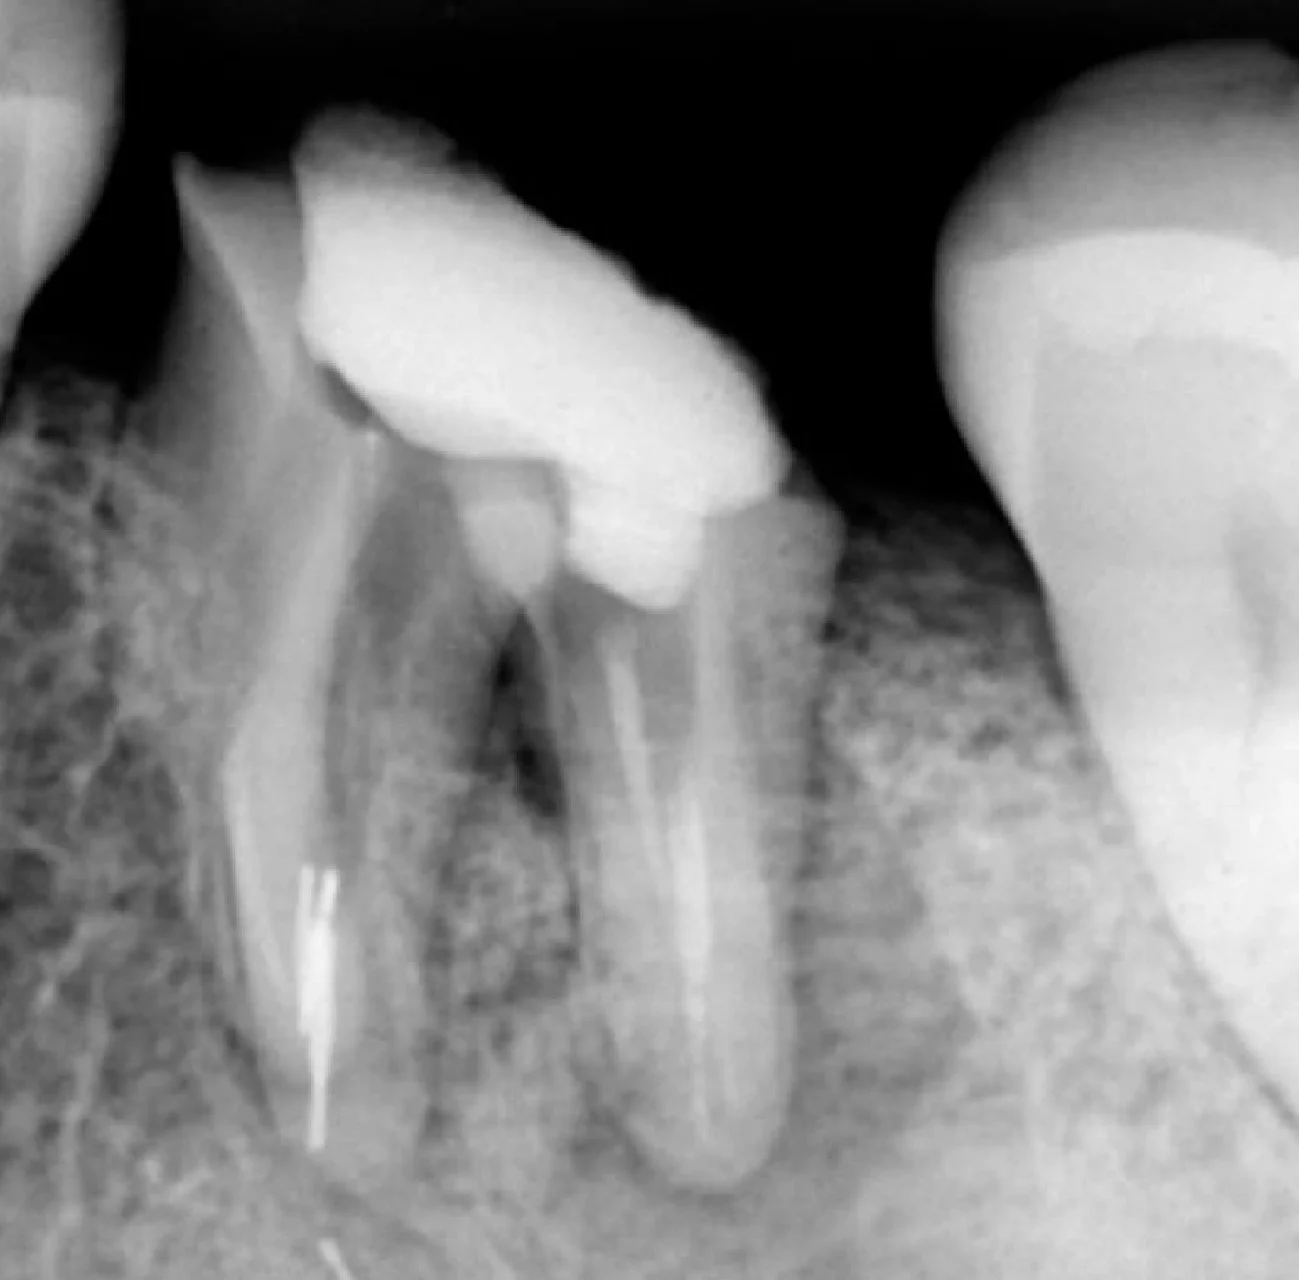

Remoção de Limas

RX inicial

RX após remoção das limas

Instrumentos (LIMAS) removidas